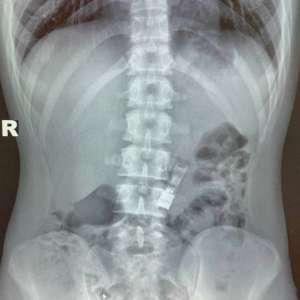

В Подмосковье 16-летний школьник случайно проглотил флешку с домашним заданием по информатике

Парень надеялся, что она выйдет естественным путем, но этого не случилось. В итоге он обратился в Детский клинический центр. Там врачи извлекли инородный предмет из его желудка с помощью щипцов.

Флешка не пострадала, и школьник успел сдать домашку.